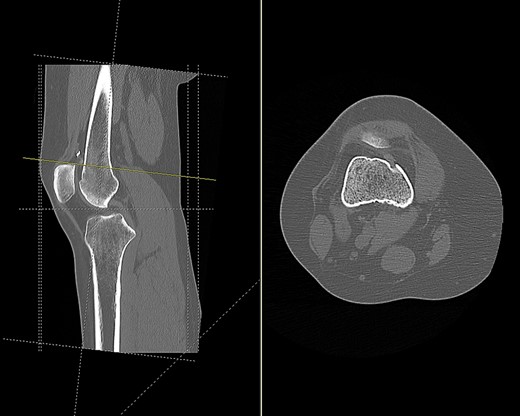

Imaging enabled assessment of the graft tunnels (Figs 2 and 3). It appeared that an oblique tunnel had been drilled from the medial epicondyle to the anterior cortex of the femur at the level of the suprapatellar fat pad.

CT scan of the right knee showing entry point and oblique path of femoral tunnel at medial epicondyle (sagittal and axial view).